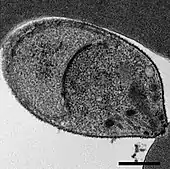

Malaria is traditionally diagnosed by examining Giemsa-stained blood films under a microscope; however, differentiating P. knowlesi from other Plasmodium species in this way is challenging due to their similar appearance.[11] P. knowlesi ring-stage parasites stained with Giemsa resemble P. falciparum ring stages, appearing as a circle with one or two dark dots of chromatin.[16] Older trophozoites appear more dispersed, forming a rectangular-shape spread across the host cell called a "band-form" that resembles the similar stage in P. malariae.[16] During this stage, dots sometimes appear across the host red blood cell, called "Sinton and Mulligans' stippling".[16] Schizonts appear, similarly to other Plasmodium species, as clusters of purple merozoites surrounding a central dark-colored pigment.[16]